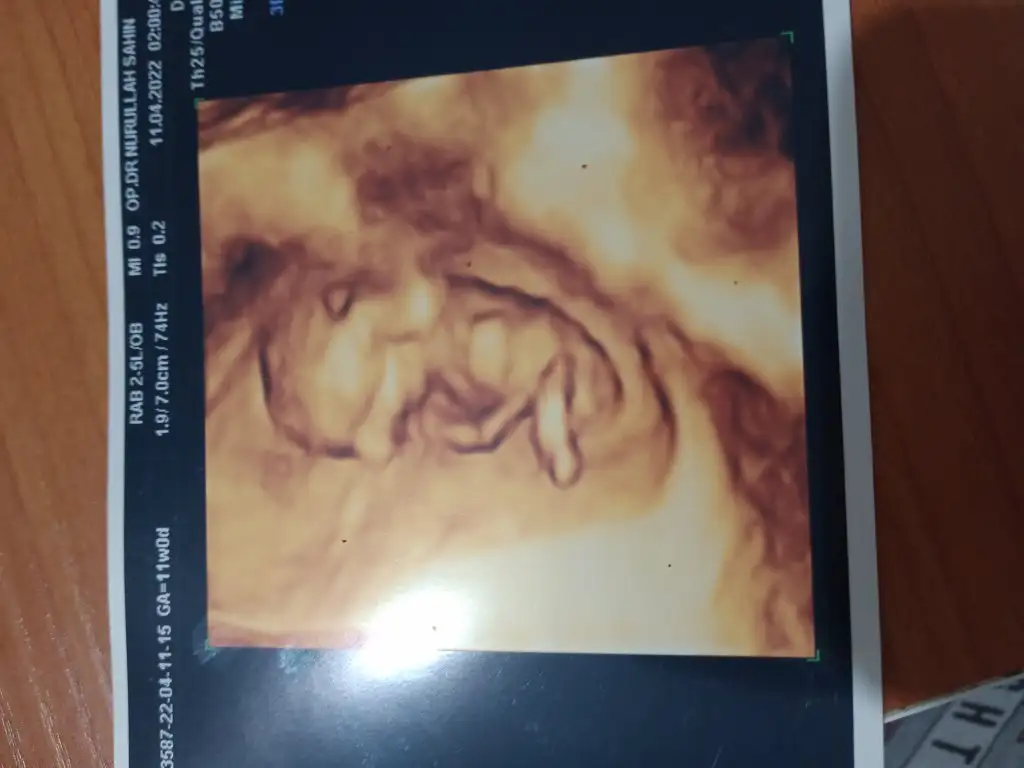

• IMG-20220411-WA0000.webp

IMG-20220411-WA0000.webp

19,3 KB · Görüntüleme: 67

• IMG20220411172226.webp

IMG20220411172226.webp

20,2 KB · Görüntüleme: 73

Tam 9. Haftada karından ultrason görüntüsü. Cinsiyeti ne olabilir, ben de merak ettim😊 Pasha22 Pasha22